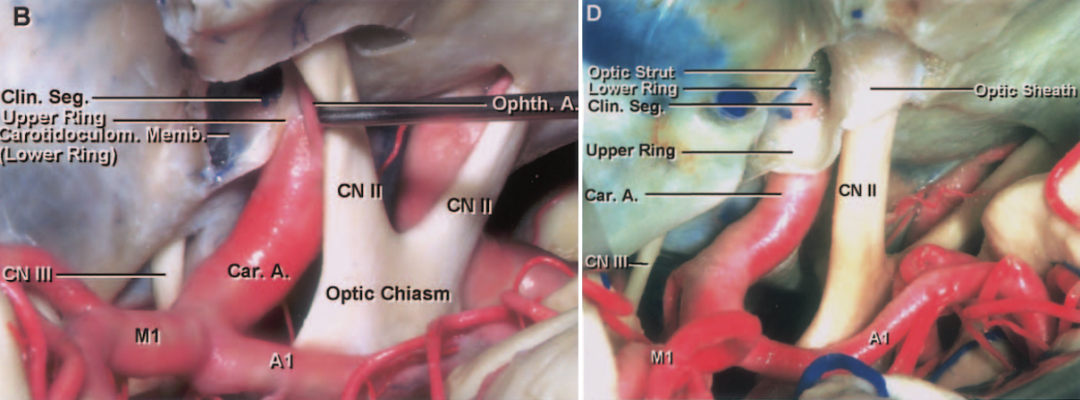

今日与大家分享的是《正海-妙术视界》第二百三十三期,由南京脑科医院何升学主任医师带来的Dolenc入路和颈部颈动脉逆向抽吸技术处理床突旁大动脉瘤2例,欢迎观看、分享。

科内讨论后认为:患者颈内动脉床突旁大动脉瘤诊断明确,患者动脉瘤破裂出血,需急诊手术治疗。术中应先在颈部暴露颈内动脉。采用Dolenc入路硬膜外磨除前床突及视神经管。术中注意保护好眼动脉。暴露动脉瘤后可孤立动脉瘤,并在颈部穿刺颈动脉并逆向抽吸,降低动脉瘤的张力后塑形夹闭动脉瘤。